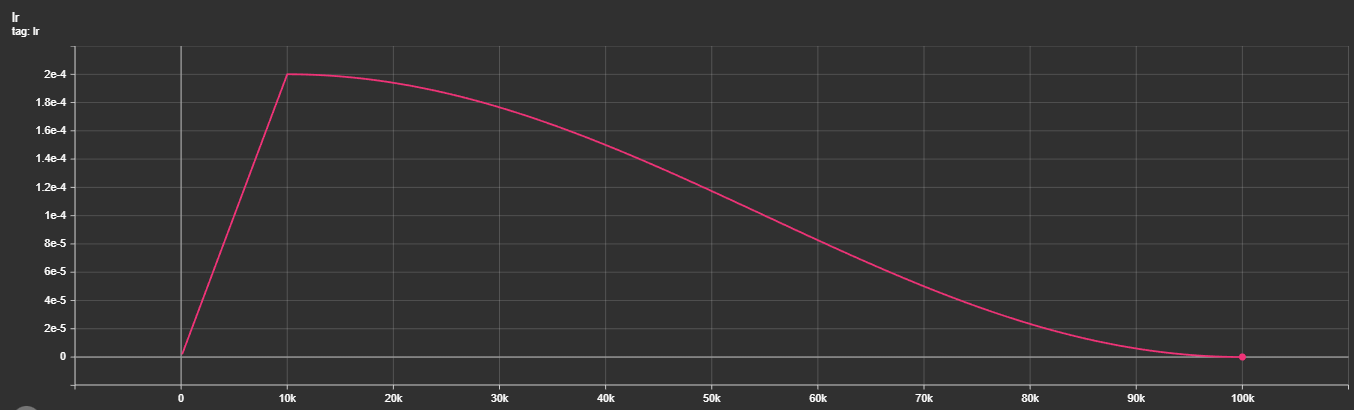

It is at this point that the post's title image comes into play. This is my first training run of a large model (specifics will be discussed in a later, probably next, post) with DDIM reverse diffusion, with 1000 timesteps, but a respacing of the timesteps to 250 (reducing the compute load by 4x). The image, for now, contains a bug from the days of having trained using only 100 timesteps, but this will be fixed shortly (in case you happen to read this in the interim, 👋). But what you can see, is how I have image masks generated via diffusion that dont look absolutely useless! Now, there's still a lot to tune here: the images being fed, augmentations, the model architecture can and will be updated, the learning rate annealing parameters tuned and the diffusion parameters as well, but for the first time, we have Sparks of Diffusion. ⚡

The direction forward is still open: I'm experimenting with the training hyperparameters (learning rate scheduler, rate, batch size, augmentation) as well as with the model architectural hyperparameters and loss functions while currently remaining bound to the MedSegDiff architecture that we started our experiments out with. I'm planning to expand to other architectures the moment I start catching a signal and figuring out what combination of parameters would lead to results starting to catch on.